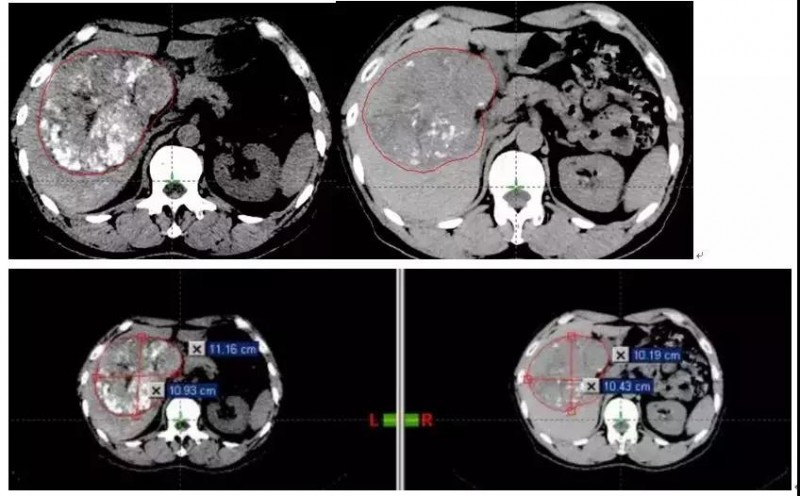

CT检查图像:治疗前(左)与治疗后(右)对比

质子治疗前该层面肿瘤大小约10.93*11.16cm,质子治疗一个月后约10.43*10.19cm;质子治疗前体积约为860.06cm3,质子治疗一个月后肿瘤体积约为702.69cm3,肿瘤缩小约157.37cm3,症状明显改善。三个月后复查肿瘤依旧在缩小,患者无其他副作用,完全可以正常生活。